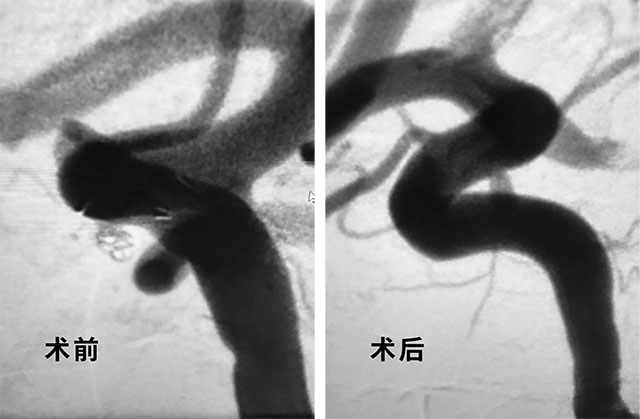

随后,在蔡女士和家人了解了两种手术方法利弊后,他们更倾向于介入治疗。在获得患者和家属全力支持,手术准备就绪后,张琪主任在医护团队的协助下于3月19日,为患者进行了动脉瘤介入栓塞术。张琪博士顺利为患者填入弹簧圈,再置入支架,完全释放后,造影显示动脉瘤无显影,支架覆盖良好,载瘤动脉通畅,撤出微导管输送系统,手术历经2个小时,顺利结束。

▲ 术后栓塞成功,造影显示动脉瘤无显影